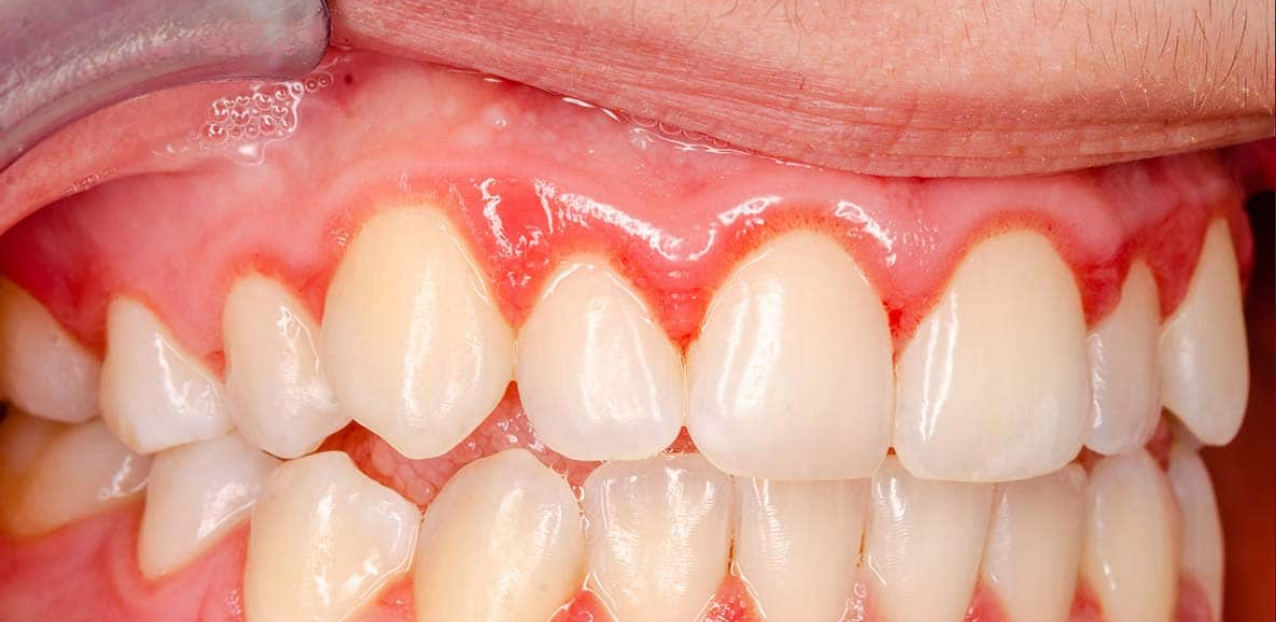

En temps normal, des gencives saines sont fermes et de couleur rose pâle.Voici quelques exemples de symptômes qui peuvent être révélateurs de l’apparition de maladies parodontales :

- des inflammations, rougeurs et gonflements des gencives,

La gingivite est une infection dentaire très courante. Certains signes avant-coureurs doivent vous alerter : un gonflement, une rougeur ou un saignement au niveau de la gencive. Il faut alors consulter rapidement votre dentiste pour éviter que la gingivite n’entraîne des problèmes parodontaux.